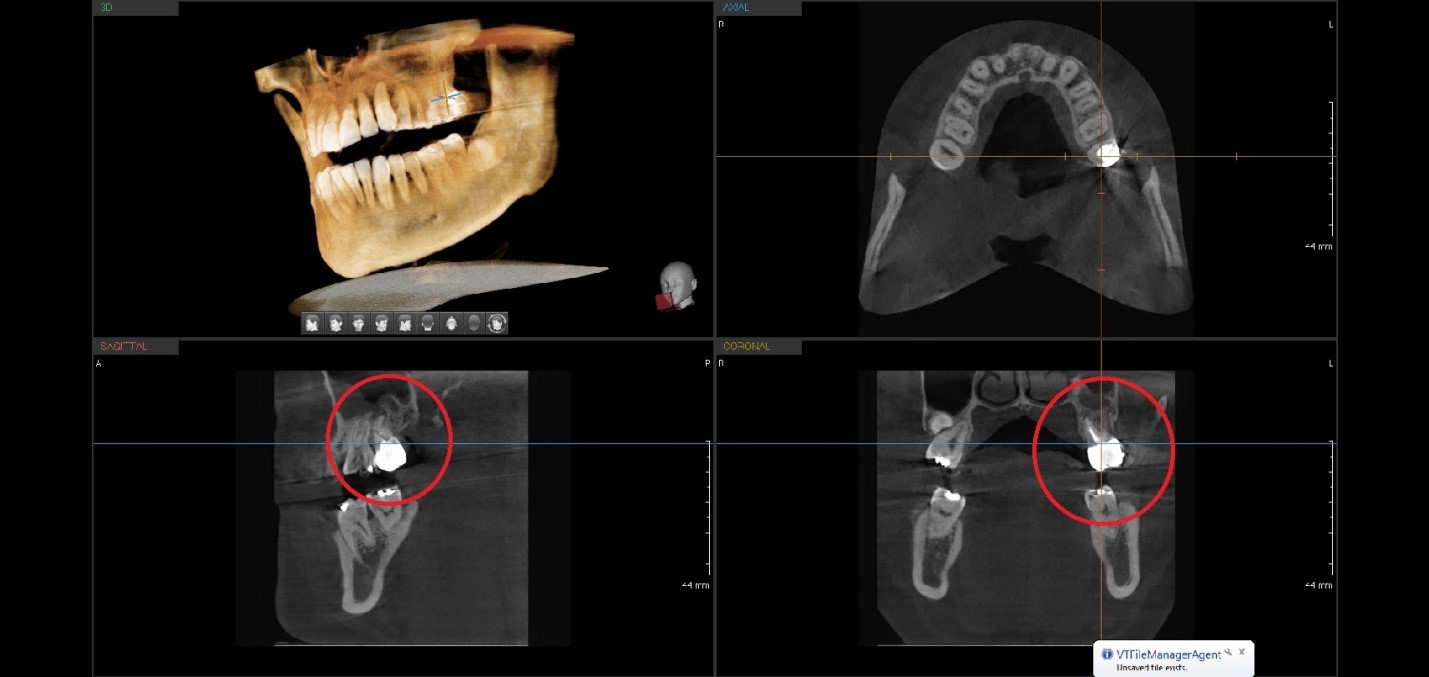

Вся информация по данным дентальной объемной томографии может служить не только прекрасным навигатором при подготовке к операции стоматологической имплантации, эндодонтического лечения (Рис.2,3 ), но и составляет часть юридической документации, которая впоследствии может рассматриваться экспертами как дополнительные возможности в связи с профессиональной спецификой. Точно определять степень причиненного вреда здоровью граждан.

Рис.2 Ez3D-i V4.3.0 данные конусно-лучевой томографии от Vatech при планировании эндодонтического лечения 26 зуба. Воспалительный процесс в левой верхнечелюстной пазухе.